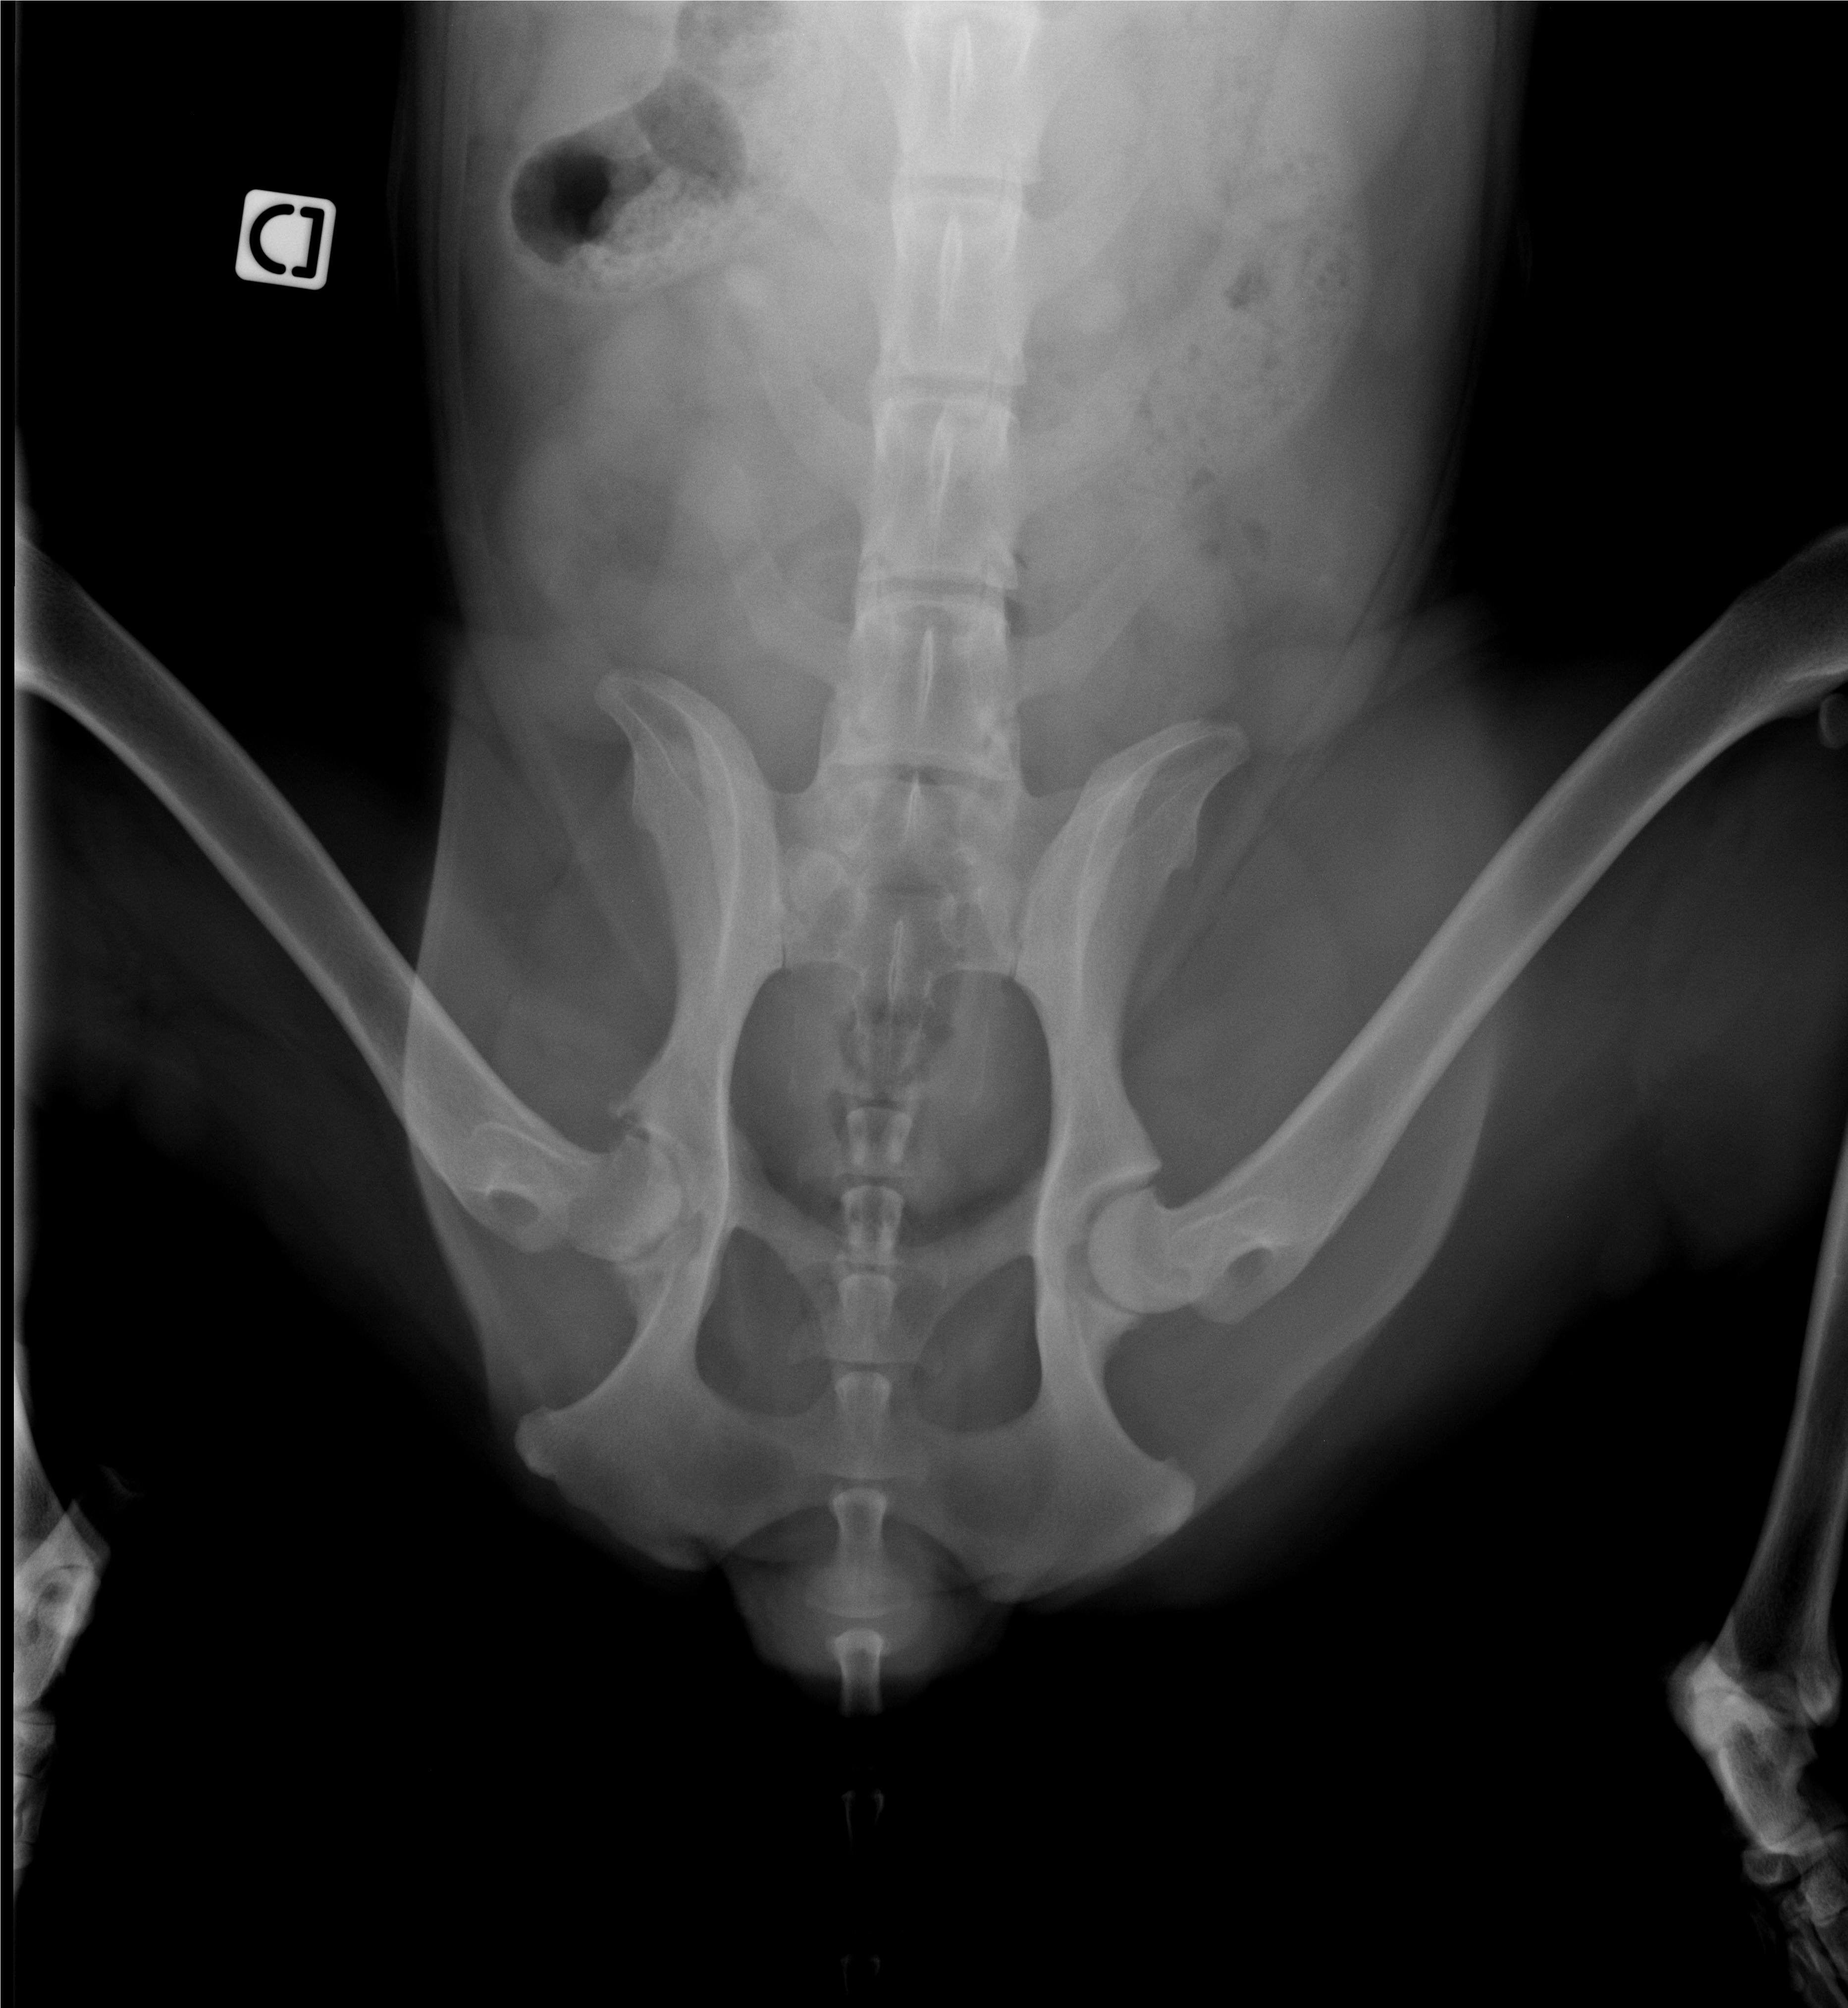

Donc il y a plus de trois semaines Hyole s'est remise à boiter fortement du jour au lendemain sans aucun signe avant. 20 jours d'anti inflammatoires et aucune amélioration , radios et le verdict tombe , la tete du fémur se désagrège comme la hanche et le cartilage n'existe plus .

La fonte musculaire est totale .

Les radios Dysplasie fin d'alphabet